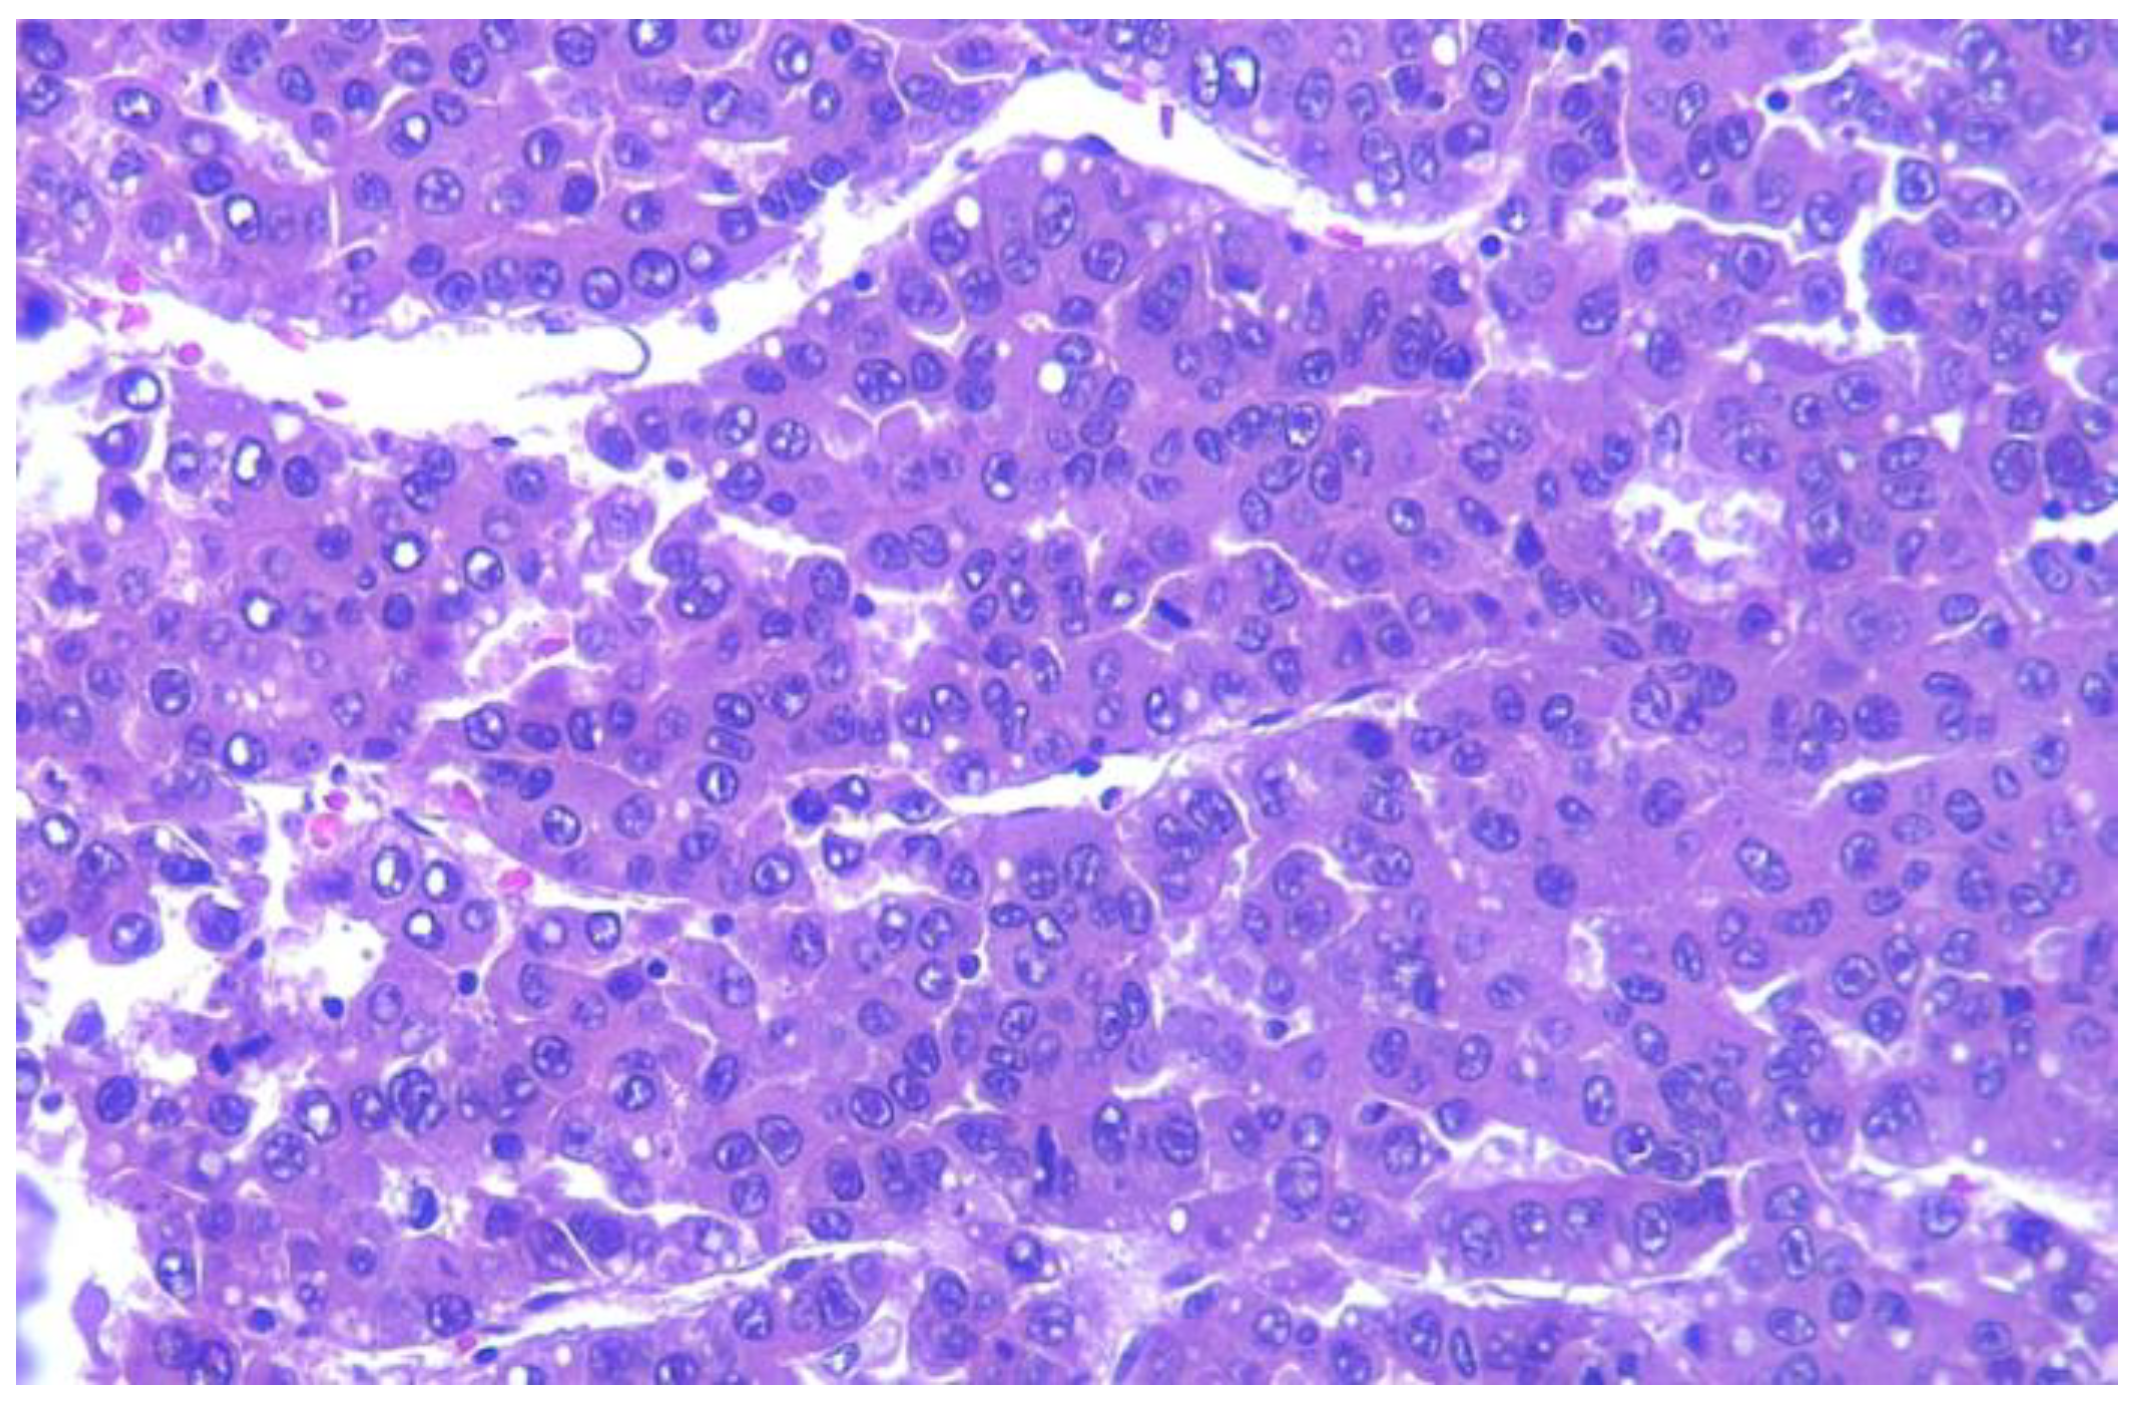

4.3. Differential Diagnosis, Comorbidities, and Malignant Transformation in BSA